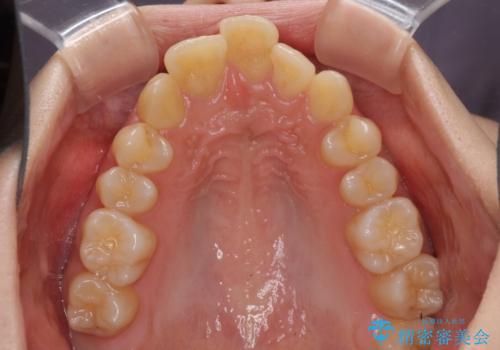

出っ歯を治したい ワイヤー装置による抜歯矯正

- 上下の出っ歯を気にして来院された患者様です。

口元を積極的に引っ込めるために、上下左右の小臼歯を4本抜歯することとしました。

右上前から2番目の歯が欠損しているため、①矯正治療により欠損部にスペースを作りインプラント補綴を行って前歯を左右対称に揃える、②左右非対称となるが、欠損補綴を行わずに排列する、のいずれかとなりますが、患者様と相談の上②にて矯正治療を行うこととしました。

変則的な歯列であったため、奥歯がしっかりと咬み合うのか、前歯はしっかりと排列できるのかと不安ではありましたが、結果としてはきれいに整った歯列にて終了することができました。